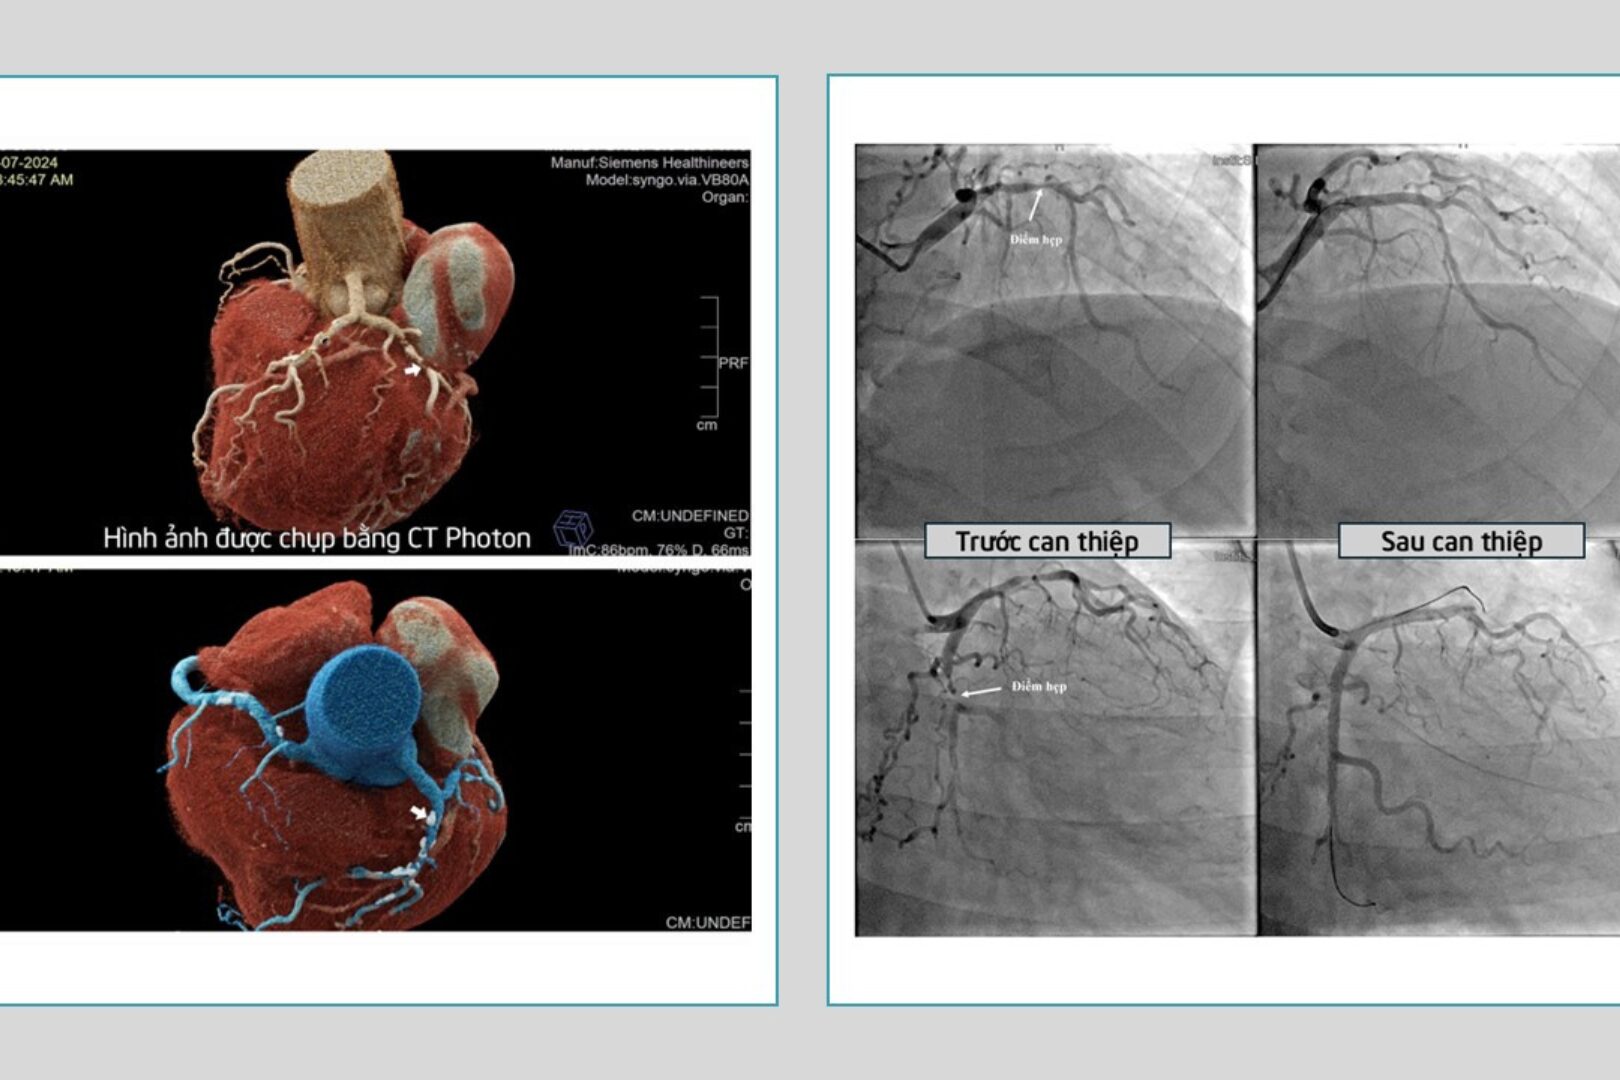

Hình ảnh vị trí mạch vành bị tắc và hẹp (Ảnh: BVCC)

Tại Bệnh viện Đa khoa Quốc tế S.I.S Cần Thơ, quan thăm khám kết hợp cận lâm sàng, các bác sĩ kết luận ông Y bị nhồi máu cơ tim cấp với men tim tăng, hình ảnh trên CT Photon cho thấy tắc nghẽn 2 nhánh mạch vành.

Sau khoảng 60 phút can thiệp, ê-kíp đã đặt thành công 2 stent ở 2 vị trí mạch vành đang bị hẹp nặng và tắc, giúp tái thông hoàn toàn mạch máu nuôi tim.